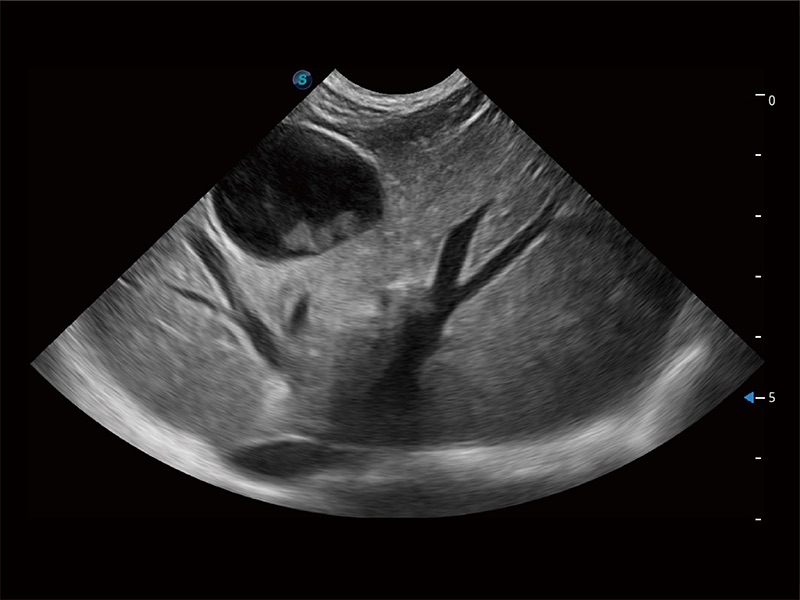

高性能和先进的临床应用工具可以为动物医生提供临床信心。ProPet 80 搭载了先进的腹部和浅表应用工具,帮助医生在日常临床实践中发挥前所未有的作用。

极大提升超低速微细血流的检出能力,同时更精准地滤除软组织和超声信号,为兽用医生提供以往无法通过常规血流获得的疾病诊断信息。

非线性融合造影成像充分利用谐波和基波信号,为难以观察的血流进行增强显像。可用于线阵、凸阵、微凸阵、相控阵探头。